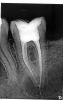

dima00 Опубликовано 18 августа, 2009 Автор Поделиться Опубликовано 18 августа, 2009 А как вы определили, что это бывшая грануллема (фото снимка к сожалению получилось не очень контрастным, т.к. сложно сфотографировать рентген-снимок), я просто боюсь, что это гной, перед удалением вроде бы грануллема была меньше (снимок перед удалением зуба 37 прикрепил к этому сообщению, качество лучше, т.к. его делали в другой поликлинике и результат дали распечатанным на бумаге) Большое спасибо за ответ Ссылка на комментарий

Bier Опубликовано 18 августа, 2009 Поделиться Опубликовано 18 августа, 2009 думаю, что боли не связаны с удаленным зубом.Скорее всего там все у вас заживает. На новом снимке мы еще видим старые границы костной ткани, отсюда и предположил о гранулеме. Ссылка на комментарий

dima00 Опубликовано 18 августа, 2009 Автор Поделиться Опубликовано 18 августа, 2009 Извините наверное я плохо выразился: я имел ввиду как вы определили, что это именно бывшая грануллема, а не гной, т.е. что это до сих пор не является грануллемой, ведь на снимке она такая же как и до удаления зуба или может я чего не увидел? Ссылка на комментарий

Bier Опубликовано 19 августа, 2009 Поделиться Опубликовано 19 августа, 2009 это всегда была гранулема а не гной. после удаления зуба гранулема либо вынимается вместе с зубом либо потом исчезает сама. По этому думаю, что у вас все ок, просто мало времени прошло. Ссылка на комментарий